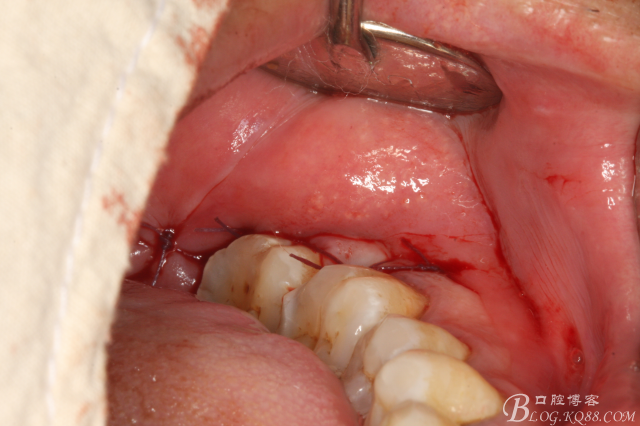

圖1. 口內(nèi)38完全埋伏